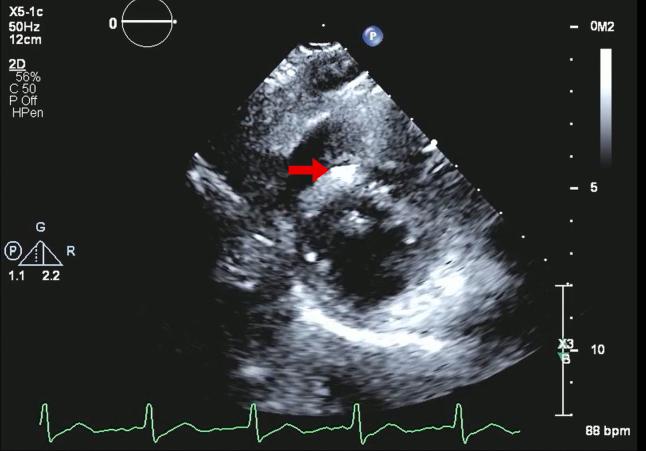

Transthoracic Echocardiography-Assisted Identification of Coronary Air Embolism During Coronary Angiography.

• CAE is a rare, high-risk morbidity and mortality event. • TTE is useful for the detection of intramyocardial air caused by CAE. • Management involves 2 core principles: increase gas diffusion and pressure.